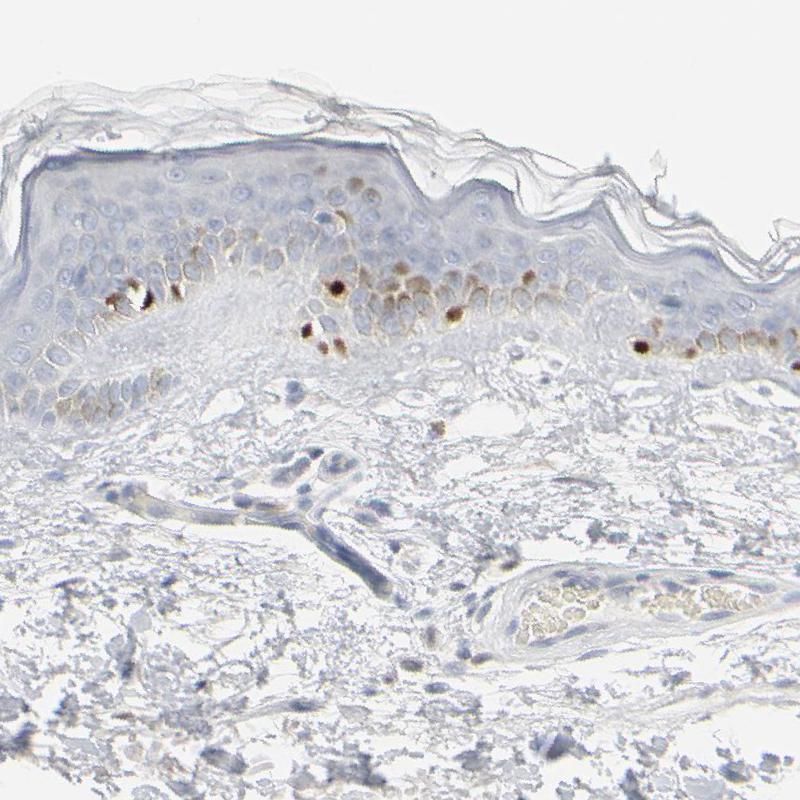

Immunohistochemistry analysis in human skin and pancreas tissues using HPA003259 antibody. Corresponding MITF RNA-seq data are presented for the same tissues.